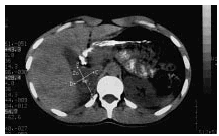

En la TC abdominal (fig. 1) se apreció una masa en la glándula suprarrenal derecha de 5,5 * 4 * 7 cm; con una zona de hipodensidad central que podría corresponder a una necrosis tumoral. Las catecolaminas y sus metabolitos se encontraban elevados en la orina, así como la noradrenalina plasmática. Se practicó una gammagrafía con metaiodobencilguanidina, observándose una captación patológica en la región suprarrenal derecha; en el tórax y el abdomen no se encontraron focos ectópicos. La ecocardiografía evidenció una hipertrofia concéntrica del ventrículo izquierdo con espesores de 18 mm en el tabique interventricular y 17 mm en la pared posterior, siendo la fracción de eyección del 56%. Todos estos resultados eran compatibles con feocromocitoma hiperfuncionante. Se intervino quirúrgicamente sin incidencias, siendo el diagnóstico anatomopatológico de feocromocitoma suprarrenal derecho. En revisiones posteriores se ha normalizado la PA y ha desaparecido la sintomatología adrenérgica. Los signos de miocardiopatía hipertrófica han desaparecido, observándose actualmente una fracción de eyección del 70% y un espesor del tabique interventricular y la pared posterior de 10 y 9 mm, respectivamente.

Fig. 1. TC abdominal que pone de manifiesto la presencia de una masa en la glándula suprarrenal derecha.